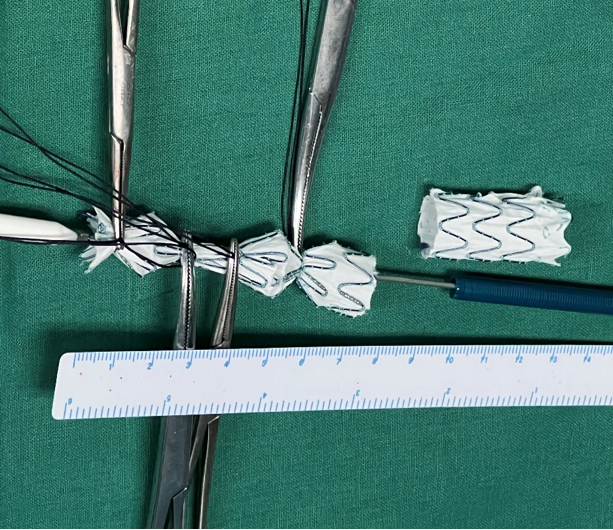

支架改装:体外释放腹主支架主体,将长的髂腿与短髂腿剪齐,然后重新装入输送系统。对于有短主体的IBD,可以无需体外剪裁。

本技术采用长度为80mm(L2)的IBD支架,以兼顾重合和缩短覆盖长度

确保支架间重叠30mm(L1),以降低内漏风险

使用4枚IBD支架(IB-1612、IB-1412等)重建SMA、CA、双肾动脉。

① 主体支架系统体外完全释放,剪除部分长腿与短腿平齐,长约3.5cm,后重新装配回收。

① 髂动脉分叉支架系统(IB-1612-030-100,G-iliac)体外完全释放。

② 于髂内动脉分叉支架远端3cm处剪断,后重新装配回收。

① 取髂动脉分叉支架系统(IB-1412-030-100,G-iliac)同法改装。